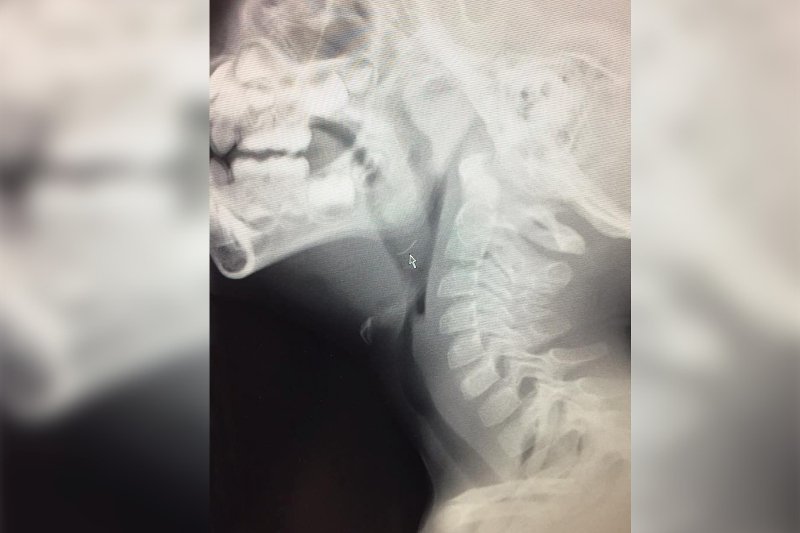

Grillować każdy lubi, trudno sobie wyobrazić lato bez spotkań ze znajomymi przy pieczonej kiełbasce czy cukinii. O ile korzystamy ze specjalnych tacek nie powinno się wydarzyć nic złego, łatwiej też zadbać o czystość grilla. Gdy kładziemy jednak żywność bezpośrednio na ruszt, musimy liczyć się z tym, że skapujący tłuszcz będzie trudny do usunięcia. Do tego właśnie służą druciane szczotki, które dzięki ostrym zakończeniom są w stanie "zdrapać" zaschnięty i przypalony tłuszcz.Takiej właśnie szczotki użyła Jenna Kuchik, kiedy chciała przygotować posiłek dla swojej rodziny. Wyczyściła ruszt i po oczyszczeniu od razu położyła na nim kawałki kurczaka. Gdy podała synowi grillowane mięso ten po kilku kęsach zaczął przeraźliwie płakać. Widać było, że coś utkwiło mu w gardle i wywołuje dokuczliwy ból. Kobieta wraz z mężem natychmiast zawieźli dziecko do szpitala, a tam wykonano prześwietlenie. Okazało się, że w gardle dziecka utkwiły małe, metalowe szpileczki, które okazały się fragmentami szczotki. Jenna była w szoku, zupełnie nie zdawała sobie sprawy, że w czasie czyszczenia grilla pozostawiła na nim metalowe opiłki, tzw. szczecinę. Na szczęście dzięki szybkiej reakcji lekarzy, udało się usunąć ostre przedmioty z przełyku. Strach, który towarzyszył matce przez tych kilka godzin sprawił, że postanowiła ona podzielić się swoją historią z innymi rodzicami.